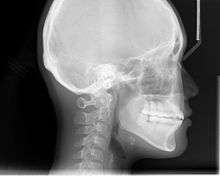

Cephalometric radiographs

Cephalometric analysis depends on cephalometric radiography to study relationships between bony and soft tissue landmarks and can be used to diagnose facial growth abnormalities prior to treatment, in the middle of treatment to evaluate progress or at the conclusion of treatment to ascertain that the goals of treatment have been met.[5] A Cephalometric radiograph is a radiograph of the head taken in a Cephalometer (Cephalostat) that is a head-holding device introduced in 1931 by Birdsall Holly Broadbent Sr. in USA[6] and by H. Hofrath

in Germany. The Cephalometer is used to obtain standardized and comparable craniofacial images on radiographic films.

Lateral cephalometric radiographs

Lateral cephalometric radiograph is a radiograph of the head taken with the x-ray beam perpendicular to the patient's sagittal plane. Natural head position is a standardized orientation of the head that is reproducible for each individual and is used as a means of standardization during analysis of dentofacial morphology both for photos and radiographs. The concept of natural head position was introduced by C. F. A. Moorrees and M. R Kean in 1958 and now is a common method of head orientation for cephalometric radiography.

Registration of the head in its natural position while obtaining a cephalogram has the advantage that an extracranial line (the true vertical or a line perpendicular to that) can be used as a reference line for cephalometric analysis, thus bypassing the difficulties imposed by the biologic variation of intracranial reference lines. True vertical is an external reference line, commonly provided by the image of a free-hanging metal chain on the cephalostat registering on the film or digital cassette during exposure. The true vertical line offers the advantage of no variation (since it is generated by gravity) and is used with radiographs obtained in natural head position.